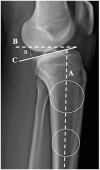

Background: Static anterior tibial translation (SATT) represents the amount of anterior translation due to axial load. It has been shown to be increased with anterior cruciate ligament (ACL) rupture, meniscal tear, and increased posterior tibial slope (PTS). It has also been shown to be correlated with ACL reconstruction failure. ACL reconstruction alone does not improve SATT. A sagittal plane slope-correcting osteotomy improves SATT, and SATT has recently been used to define the target slope correction after osteotomy. However, absolute values for SATT differ between institutions by >5 mm. Absolute measures differ based on the amount of magnification of the image, which varies based on the radiographic source to image distance, the source to object distance, rotation, and whether the medial or lateral condyle is presented to the source first. Scaled, or percentage radiographic measures, should correct for these differences.

Purpose: To express SATT as a percentage (SATT%) of the medial plateau distance to improve accuracy and interinstitutional utilization of SATT.

Methods: A consecutive series of patients without ligamentous or meniscal injuries between 2019 and 2022 was reviewed. A matched consecutive cohort of patients with nonacute ACL injuries (surgery between 6 and 12 weeks after injury) without concomitant pathology was reviewed. Preoperative SATT and PTS were measured with a previously validated technique on lateral weightbearing knee radiographs. Regression analysis was performed to investigate the relationship between SATT% and PTS.